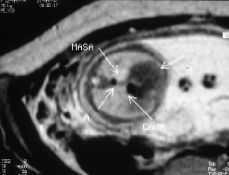

Figura 4.RX tórax recién nacido: sin hallazgos patológicos.

El control inmediato del neonato reveló una analítica normal, ecografía y radiología de tórax sin hallazgos patológicos y ecocardiograma normal. Los controles posteriores, hasta el sexto mes, han sido completamente normales, estando programado continuar con revisiones periódicas.